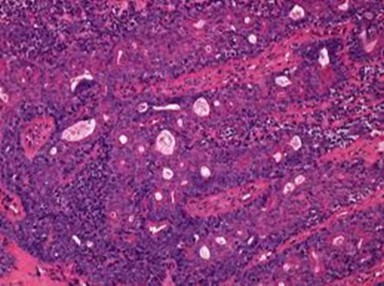

Granular arrangement of malignant cells and intercellular bridges are conspicuous with the demonstration of nuclear atypia, pleomorphism, prominent mitosis and tumour necrosis. A peripheral palisade is discernible within the cellular aggregates. Mitotic figures are common and can be quantified as up to 12 mitosis/ high power field. Tumour differentiation can prominently be of the ductal category with the demonstration of intra-cytoplasmic lumina. Comedo type tumour necrosis is evident along with foci of squamous differentiation The neoplasm is reactive to periodic acid Schiff ‘s (PAS) stain. (Figure 1, Figure 2, Figure 3, Figure 4, Figure 5, Figure 6, Figure 7, Figure 8, Figure 9, Figure 10, Figure 11, Figure 12, Figure 13.

Figure 1.Solid aggregates of tumour cells and duct structures in eccrine porocarcinoma (14).

Figure 3.Cohesive accumulations with numerous ductular articulations of carcinoma cells in eccrine porocarcinoma (15).